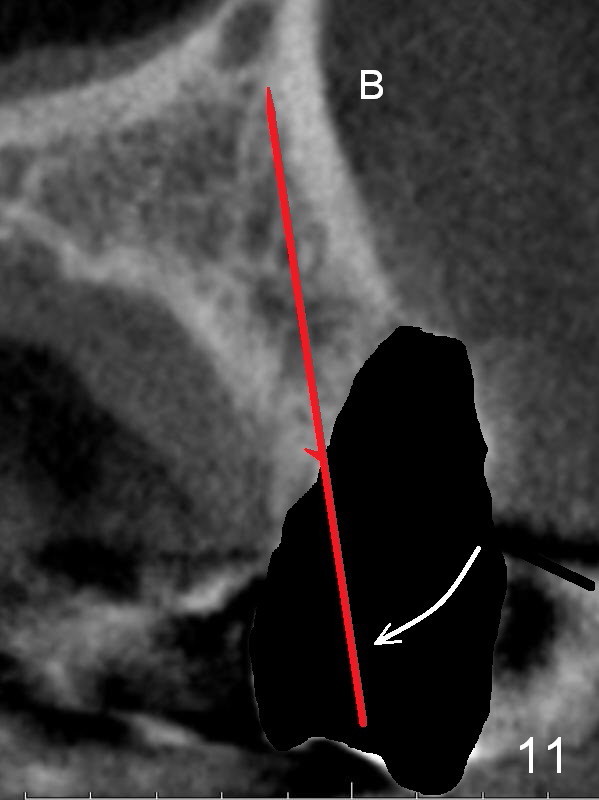

After extraction, the bottom of the socket must be oblique (Fig.9 arrowheads). As usual, osteotomy is initially at the junction of palatal (Fig.10 P) 1/3 and middle 1/3 perpendicular to the plate.  Once the drill gets engaged, the trajectory is to be changed (Fig.11 curved arrow) so that the apical end of the osteotomy (red line) is as close to the buccal plate (B) as possible.  The purpose is to keep the palatal end of the osteotomy as palatal as possible.  In spite of the effort, an angled abutment is expected, as large as 20 degree (Fig.8 purple angle).